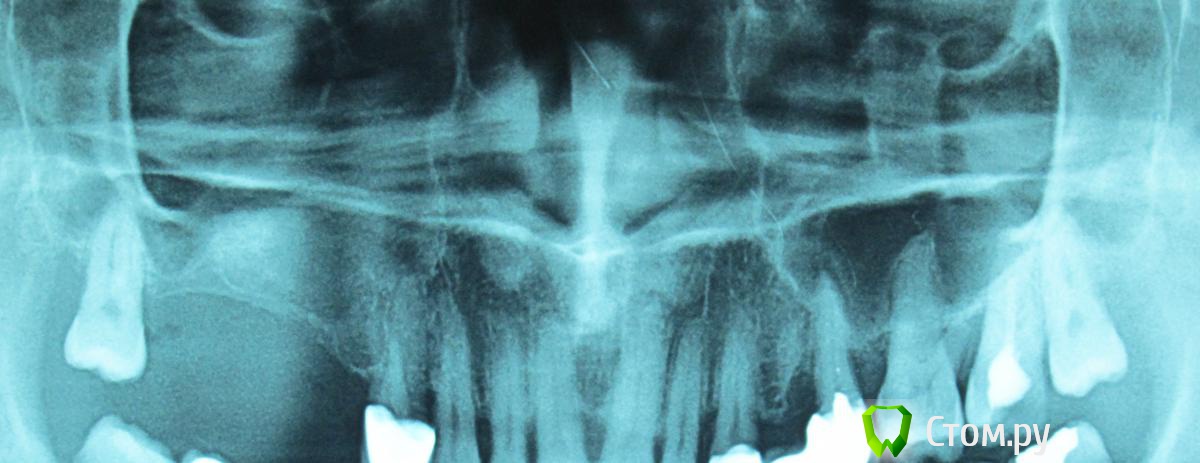

Orient Опубликовано 16 июля, 2013 Поделиться Опубликовано 16 июля, 2013 Как отличить по рентгену мукоцеле от ретенционной кисты? Ссылка на комментарий

kriokov Опубликовано 16 июля, 2013 Поделиться Опубликовано 16 июля, 2013 Как отличить по рентгену мукоцеле от ретенционной кисты?если точно выясню, отпишусь Ссылка на комментарий

АнтонТЛТ Опубликовано 16 июля, 2013 Поделиться Опубликовано 16 июля, 2013 Разговаривал вчера с лором, сказал различить можно только интраоперационно. Мукоцеле содержит муцин, он гелеобразной консистенции. Киста жидкостная. 2 Ссылка на комментарий